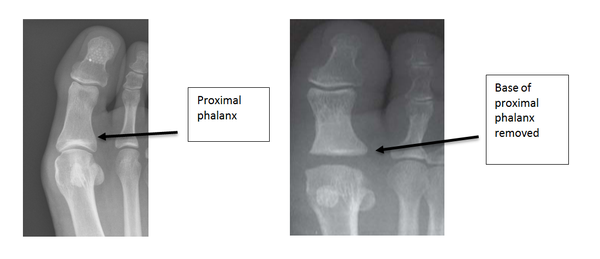

Arthroplasty

This procedure reduces the function of the big toe and can lead to weight transferring to the smaller foot joints. It has the advantage of providing some motion at the joint although the toe post-surgery is significantly shorter. This procedure is generally reserved for patients who have low levels of activity and require a short recovery time. Half of the arthritic joint is removed by resecting the base of the proximal phalanx. The operation should take away the joint pain but can leave the big toe shorter and not as stable on the ground.

Pre and post diagram